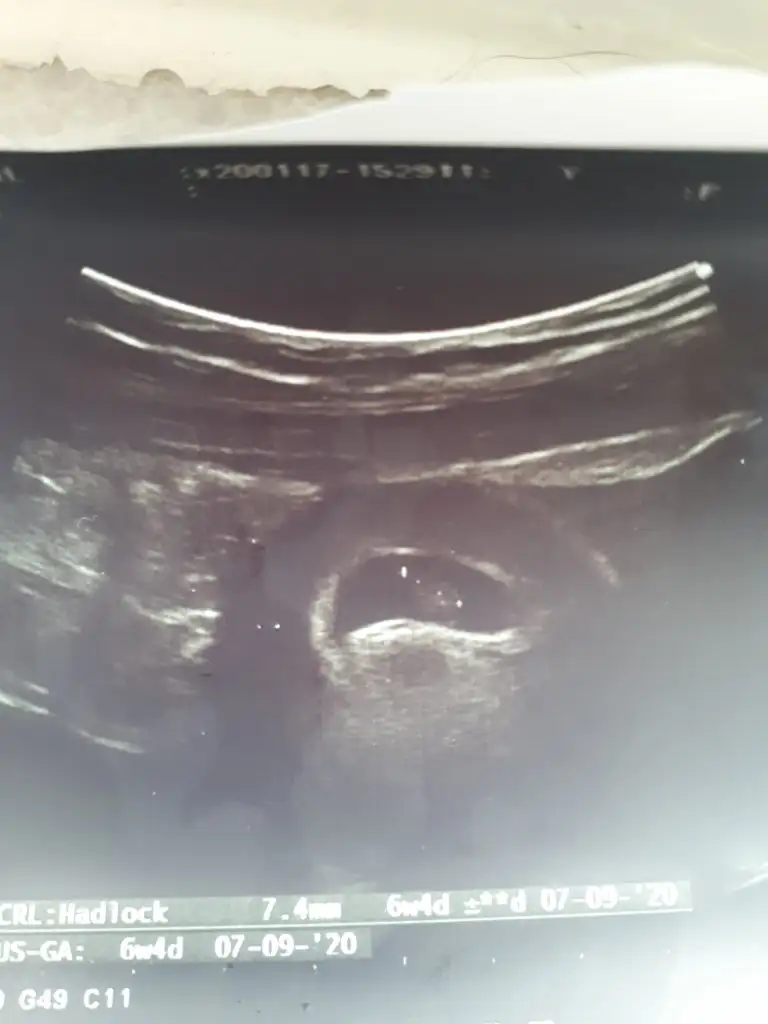

Teyzeleri benim minigimden selamlar her şey yolunda gidiyor şükürler olsun ki ama bisey sorucam 6+4 görünüyoruz 6+5 olması lazım di bir gün önden yada geriden gelmesi sıkıntı değil dimi ?

Bende 6+4 de Dr gittin kalp atışı duyamadı da Dr o yüzden sordum canım

ayben onu yiyeyim maşaallah sübhanallah kuzum benim çok şükür Elhamdülillah yok canım sorun değil ben regliye göre 6+5 olmam gerekiyor ama dün doktorda 5+5 çıktım muhtemelen geç döllenme oldu benim kızımda öyle 1 hafta geriden geliyordu ama tam zamanında doğdu anlamadım